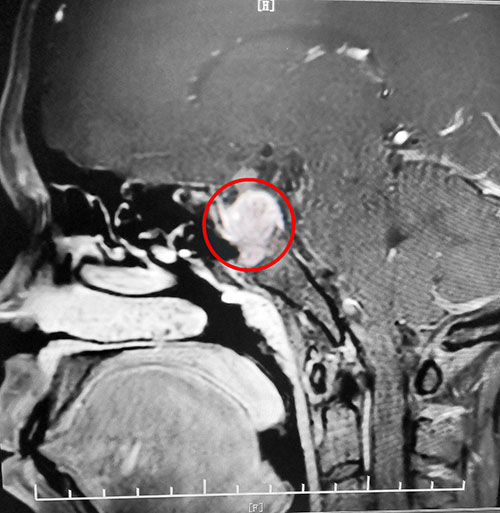

再查催乳素:1436μIU/mL。鞍區(qū)MRI平掃+增強(qiáng)顯示,蝶鞍顯著擴(kuò)大,鞍區(qū)見不規(guī)則腫塊影,大小約2.3*2.6*3.4cm。綜合各項(xiàng)檢查結(jié)合臨床,劉女士被診斷為垂體大腺瘤(垂體瘤超過1厘米就是垂體大腺瘤)。

▲影像檢查顯示:垂體大腺瘤,超蝶鞍生長